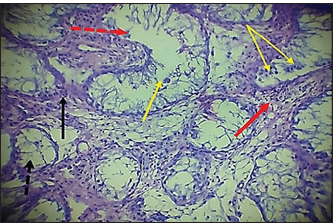

Fig. 7. Histopathological section of testes from a dog in the zinc gluconate group at 30 days post-intrasticular injection, showing exfoliation of germ cells (red arrows), infiltration of inflammatory cells (white arrows), Leydig cell clusters (yellow arrow), edema (star), and congestion (yellow head arrow) (H & E stain 10X). Surgical groupIn the surgical group (GII), the main characteristic findings at 30 days post-surgery were degeneration of seminiferous tubules, multinucleated spermatid, infiltration of inflammatory cells, atrophy of Leydig cells, and vacuole degeneration of basal and Sertoli epithelium (Fig. 8). Furthermore, there was loss of the straight shape of the tubuli recti, disequimentaion of the tubuli recti epithelium, and proliferation of myoid cells (Fig. 9). Other sections showed coagulative necrosis and ghost tubules in the rete testis (Figs. 10 and 11).

Fig. 8. Histopathological section of testes from dogs in the surgical group at 30 days post-surgery, showing degeneration of seminferous tubules (red dotted arrow), multinucleated spermatid (yellow arrows), infiltration of inflammatory cells (red arrow), atrophy of Leydig cells (black arrow), and vacuole degeneration of basel and sertoli epithelium (black dotted arrow) (H & E stain 10X).

Fig. 9. Histopathological section of testes from a dog in the surgical group at 30 days post-surgery, showing loss of the straight shape of the tubuli recti (yellow arrow), disequilibrium of the tubuli recti epithelium (black arrow), proliferation of myoid cells (red arrow), and infiltration of inflammatory cells (red dotted arrow) (H & E stain 40X).